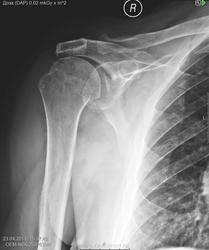

Возраст 82 года. В области головки правой плечевой кости отмечается кистовидная перестройка. Суставные поверхности акромиально-ключичного сустава отстоят друг от друга на увеличенное расстояние.

З-ие: дегенеративно-дистрофические изменения в правом плечевом суставе в виде кистовидной перестройки.

Возможно, все-же последствия старой травмы плеча, широковато сочленение

Для полной уверенности лучше сравить со здоровой рукой.

И симметричный артроз плечевых суставов есть у него. Хоть проекция на сочленение, а не на сустав, но таково моё никчёмное мнение. Ну, и ещё субакромиальный артроз. Здесь он есть. И опять симметричный. Так что пусть теперь задумаются неврологи и травматологи, что откуда и что первично - курица или яйцо.))